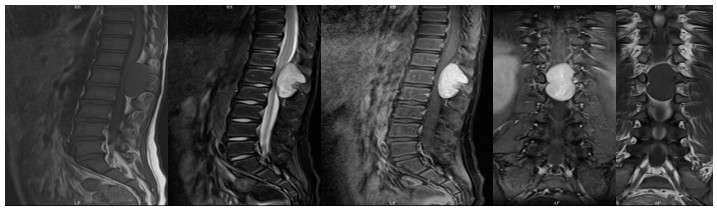

59歲鄒阿姨術前胸椎MRI檢查

10歲小孩術前增強MR

術后復查不固定位置良好